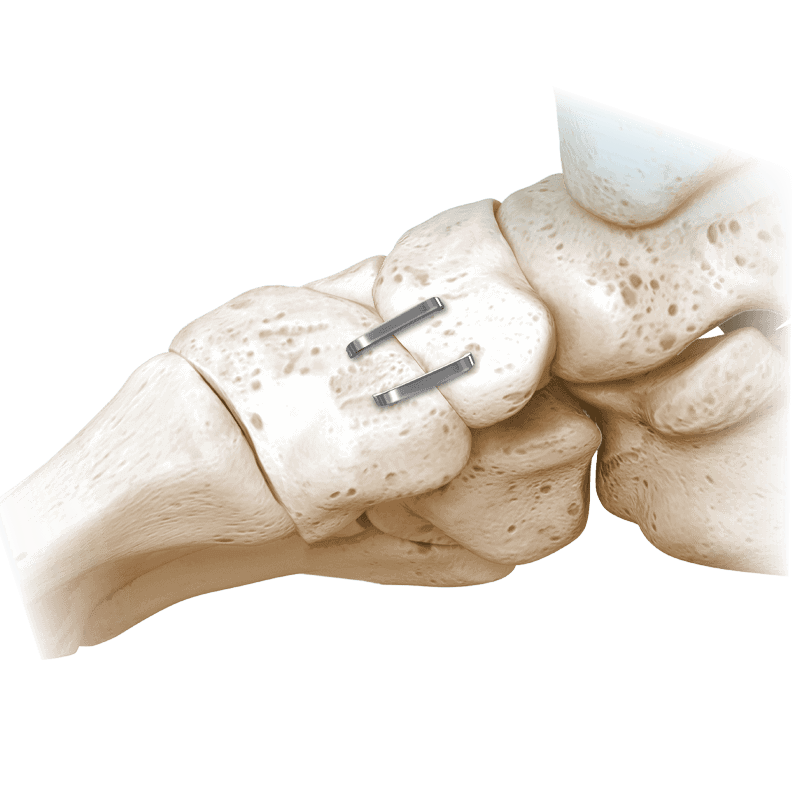

NeoSpan® SE Compression Staples

A superelastic compression-ready fixation system designed for fixation of fractures, fusions, or osteotomies